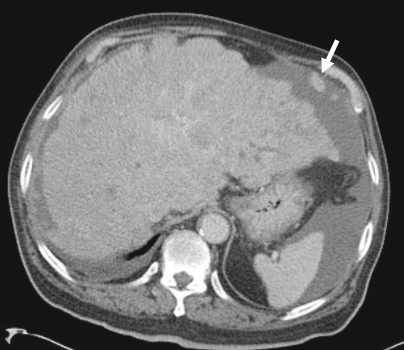

肝血管瘤为最常见的良性肿瘤,可分为海绵状血管瘤、毛细血管型血管瘤、硬化型血管瘤等。包膜皱缩为肝血管瘤的不典型表现,可见于肝硬化背景下及硬化型血管瘤,后者被认为是血管瘤退化末期,表现为透明化纤维组织替代血管周围间隙。影像上表现为 T2WI 信号减低,增强后缺乏典型填充式强化。

硬化型血管瘤,CT 表现为低密度,增强后无强化,邻近肝包膜凹陷,MRI T2-FS 序列示病灶呈高信号。该患者既往直肠癌病史,此病灶不能除外转移。活检结果为硬化型血管瘤。